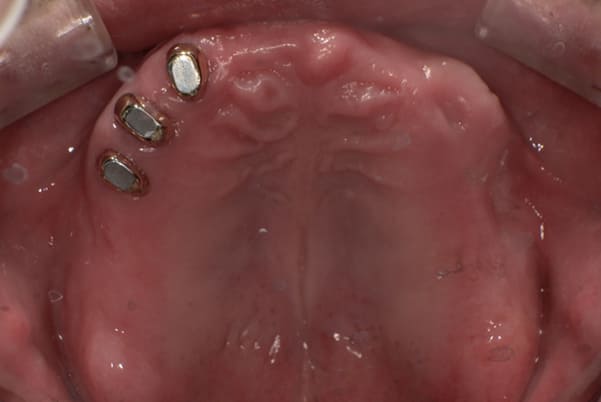

症例レポート[CASE.05]

食事ができるようになりたい

- 女性(40代)

- 食事ができない、何とかしたい

- 上顎精密金属床総入れ歯

- 下顎精密金属床総入れ歯

奥歯がなくなり、放置されたことで、かみ合わせが深く乱れた状態でした。

乱れたかみ合わせを治し、治療途中で見た目は患者様がご納得いく、歯の大きさ、色、形をご一緒に確認しながら入れ歯を最終的に作製しました。

上顎治療後

下顎治療後